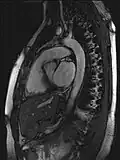

Neue, schnellere Aufnahmeverfahren ermöglichen das Scannen einzelner Schnittbilder in Bruchteilen einer Sekunde und liefern auf diese Weise eine wirkliche Echtzeit-MRT, die die bisherigen Versuche in Anlehnung an die konventionelle Fluoroskopie ersetzen. Somit können beispielsweise Bewegungen von Organen dargestellt oder die Position medizinischer Instrumente während eines Eingriffs überwacht werden (interventionelle Radiologie). Zur Abbildung des schlagenden Herzens (Abbildung rechts) werden bisher mit einem EKG synchronisierte Messungen benutzt, wobei Daten aus mehreren Herzzyklen zu vollständigen Bildern kombiniert werden. Neuere Ansätze für die Echtzeit-MRT versprechen dagegen eine direkte Herzbildgebung ohne EKG-Synchronisation sowie bei freier Atmung mit einer zeitlichen Auflösung von bis zu 20 Millisekunden.

MRT des menschlichen Herzens, Vierkammerblick; animierte Version

MRT des menschlichen Herzens, Vierkammerblick; animierte Version -

MRT des menschlichen Herzens, Sagittalansicht; animierte Version

MRT des menschlichen Herzens, Sagittalansicht; animierte Version -